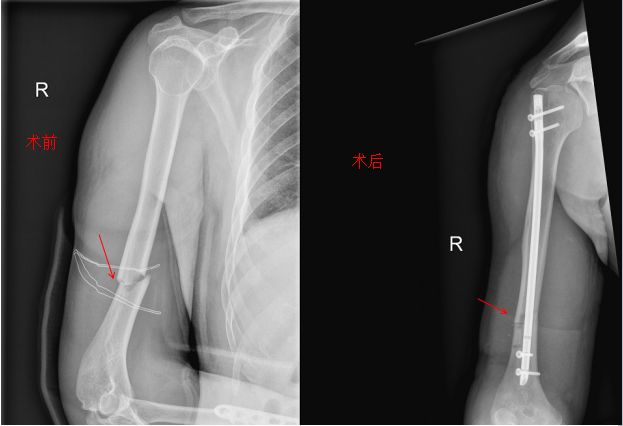

两科联手成功实施一例微创肱骨骨折髓内钉固定手术

日前,我院手足外科与骨科联手对一位多发上肢严重损伤的患者成功实施了微创肱骨骨折髓内钉固定手术。

手术中,北京航空总医院骨科副主任 、我院骨科主任石少辉(在我院挂职帮扶)亲自主刀,实施微创肱骨骨折髓内钉固定手术,这是我院就此类骨折开展的首例新技术。该技术与以前的钢板螺钉固定有几个明显优势:一是手术小切口、出血少(仅在肩峰下切口约3厘米,出血不到30毫升),患者满意度高。二是创伤小,手术时间短,由于没有进行骨折断端切开剥离,闭合复位,减少了二次创伤及感染率。三是生物力学效果佳,作为中心型交锁内固定,不仅可以控制骨折部位的轴向力线、而且可以防止骨折旋转畸形、降低了内置物断裂的风险 ,患者可以早期功能锻炼及负重。四是充分利用髓内钉弹性固定、应力分散避免应力遮挡作用等优点,避免再骨折发生。目前,该患者术后恢复良好,待手术切口愈合好即可出院。